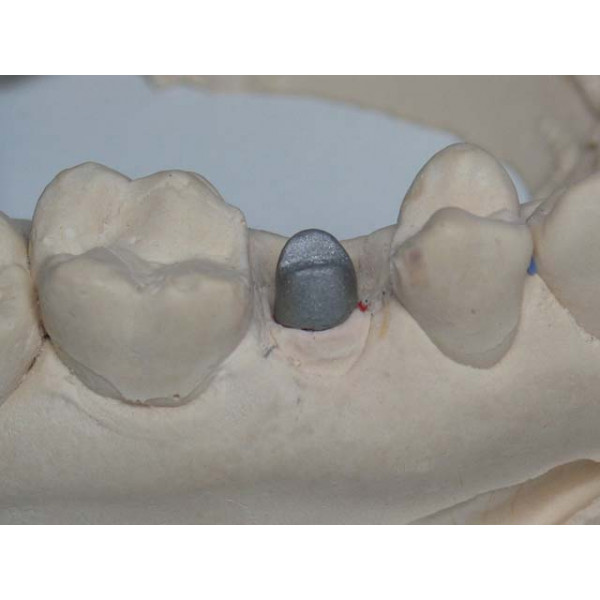

Культя зуба это

Культя зуба это 106 фото